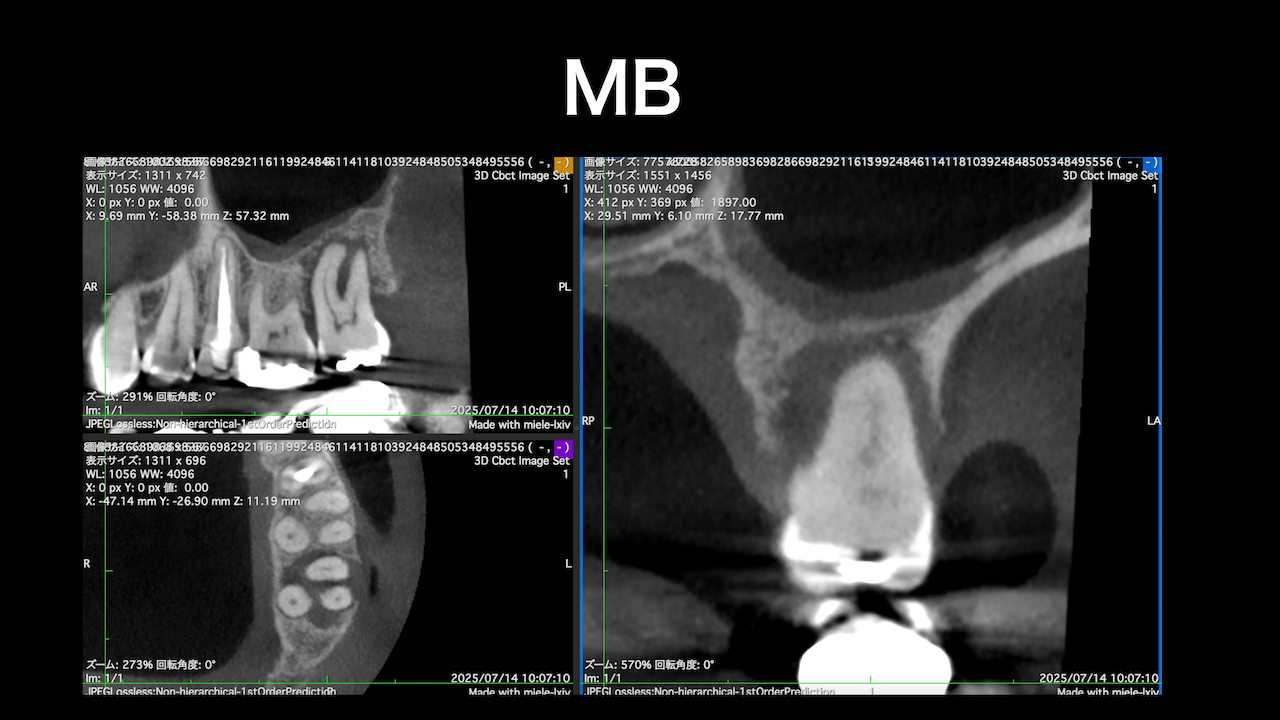

術前にCBCTを撮影したので、MB2がないということを分かった上で根管治療を行っている。

これがCBCTを歯内療法に用いる最大の利点だろう。

上手い!